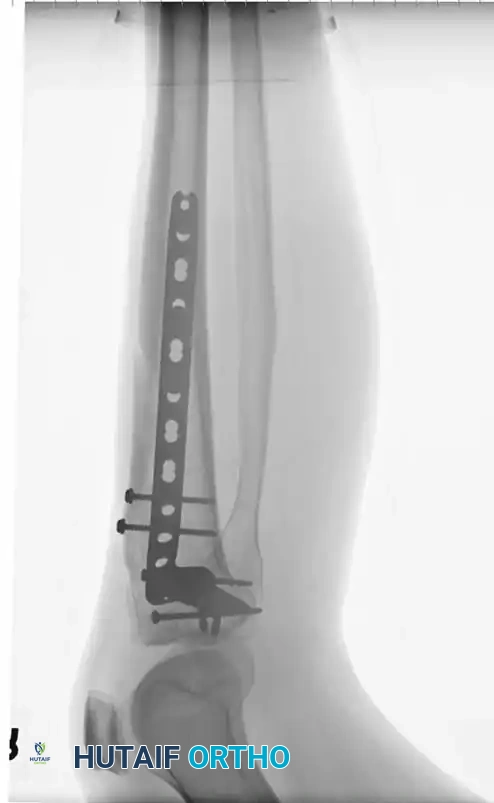

Image

Fig. 2: Clinical application of a large fragment locking compression plate in a patient with a complex fracture of the tibial shaft extending into the tibial plateau.